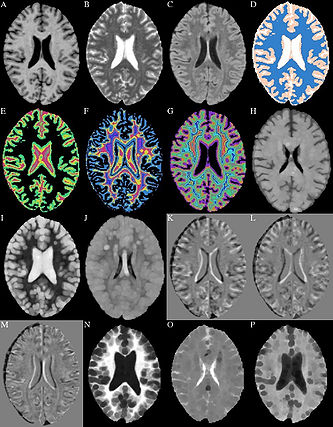

• The method makes use of local morphometric features based on multiple MR sequences, including T1-weighted, T2-weighted, and Fluid Attenuated Inversion Recovery. After preprocessing, including co-registration, brain extraction, bias correction, and intensity standardization, 49 features are calculated for each brain voxel based on local morphometry. At each level of segmenta- tion a supervised classifier takes advantage of a different subset of the features to conservatively segment lesion voxels, passing on more difficult voxels to the next classifier. This multi-level approach allows for a fast lesion classification method with tunable trade-offs between sensitivity and specificity producing accuracy comparable to a human rater.

Predicted Heat Map, Manual Segmentation, Thresholded Heat Map

• Almost completed full pipeline for longitudinal analysis which detects changes in lesions allowing for more clinical applications. The following 3 figures demonstrate some of the longitudinal functionality comparing a baseline FLAIR with a followup FLAIR. The label map shows the change in lesion voxels where gained lesion is red, recovered tissue is blue, and lesion that remained lesion is yellow.